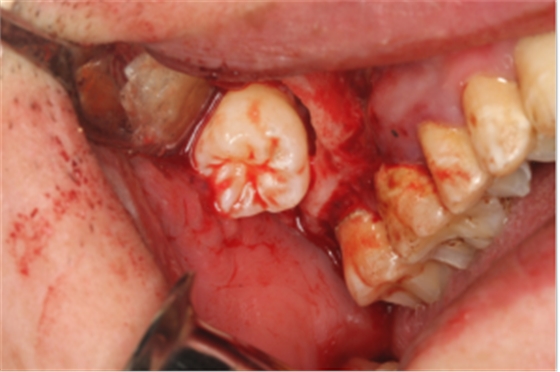

14:00-15:00 微創(chuàng)拔除阻生牙流程及精髓(結合臨床病例圖文展示)

15:00-16:30 常用的阻生牙拔除手法及技巧(切開、翻瓣、分牙、去骨、增隙、縫合等六大手術技巧)

【精彩病例】